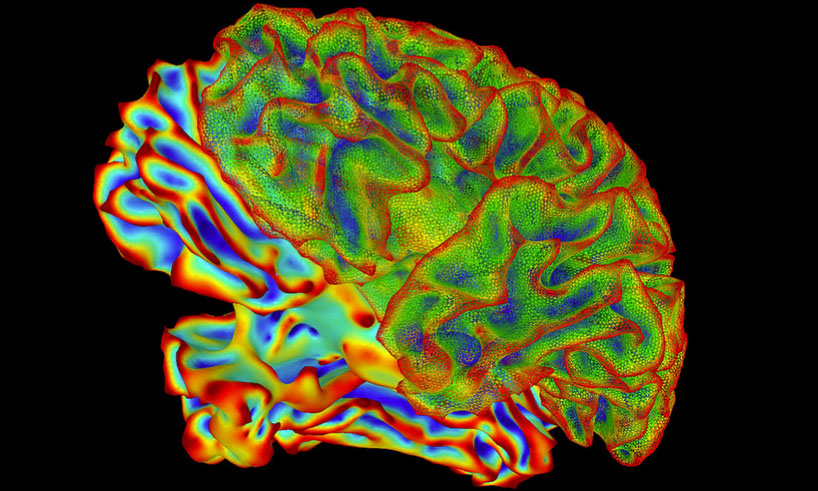

A team of University of Rochester psychologists set out to determine if real-time fMRI neurofeedback can help a person regulate neural activity in a way that might improve psychiatric illness. Their meta-analysis found that when people were shown their own brain patterns in real time, they were able to regulate activity in specific regions of the brain. (Photo: National Institute of Mental Health, National Institutes of Health)

Does neurofeedback imaging work for psychiatric patients?University of Rochester psychologists have found that real-time functional magnetic resonance imaging neurofeedback (rtfMRI-NF) can help a person regulate neural activity in a way that might improve psychiatric illness.

According to lead author Dudek, their review found that when people were shown their own brain patterns in real time, they were able to regulate activity in specific regions of the brain. “This training, known as neurofeedback, offers an exciting and novel treatment method for psychiatric illness.”

Coauthor Dodell-Feder agrees that the findings are “very promising,” especially because there are very few treatments, psychopharmacological included, that specifically target neural circuits known to contribute to psychopathology.

Yet, there are caveats: the data show less clear evidence that volitional control over the brain regions targeted by neurofeedback translates to an improvement in a person’s symptoms or cognitive impairments. For example, when analyzing the impact of rtfMRI-NF on symptoms, the team found an approximately 60 percent chance that a randomly selected person who received rtfMRI-NF showed improvement in symptoms compared to a randomly selected person who received a placebo procedure. Read more here.